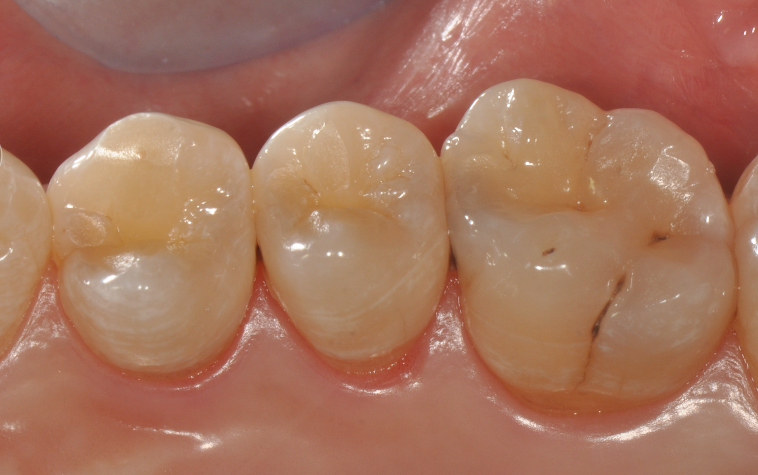

牙医-马小寒【实操病例】

右上6号牙位的近中,可见隐约龋坏